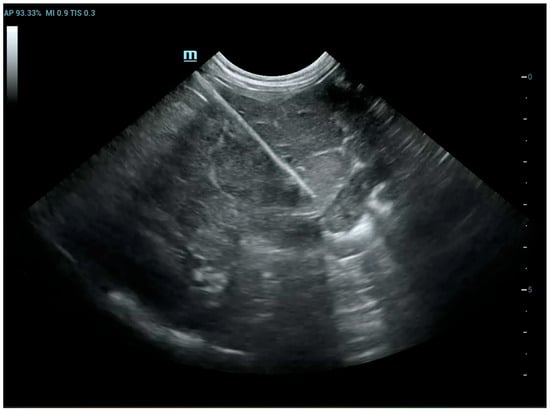

The patients included in the study underwent imaging-guided biopsies, specifically under US or CT guidance, of the masses under examination as shown in Figure 1 and Figure 2. Biopsy samples were collected using a semi-automatic spring-loaded tru-cut (14 G) in the case of soft tissue lesions and a bone needle (8–10 G) for bone tissue. These interventional diagnostic methods were performed after monitoring and anesthetizing the patient, under the continuous supervision of the anesthetist in charge. Trichotomy of the area of interest was performed, followed by surgical scrubbing with betadine and alcohol. Once the patient was prepared, a small incision was made with a number 11 scalpel blade on the skin surface, through which the tru-cut (14 G) or bone needle (8–10 G) was subsequently inserted. The biopsies were performed using ultrasound guidance or computed tomography, depending on the case, the location of the lesion and the availability of instruments.

Figure 2. Dog, Mixed breed, 13 y, spayed female. Phases of CT-guided humeral biopsy with bone window. Final diagnosis: humeral osteosarcoma.